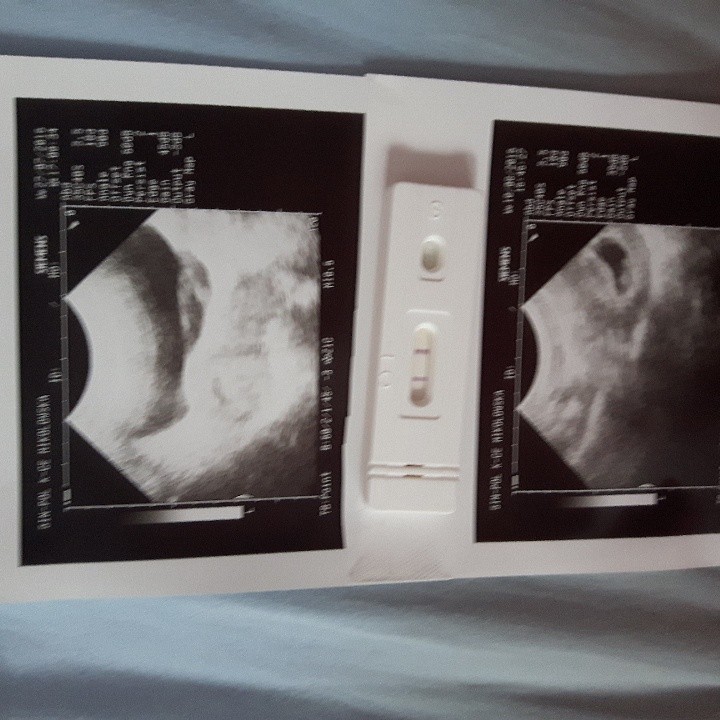

Zdj z usg z 6tc

i z 8tc :) tescik robiony tydz po spodziewanej @